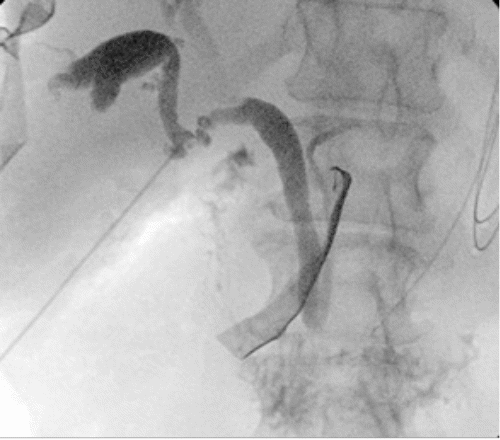

During laparoscopic cholecystectomy, the gallbladder dissection began at the fundus and progressed towards the liver bed. Upon entering the Calot's triangle, a structure resembling the cystic duct was identified, joining the common hepatic duct. However, an additional duct draining into the cystic duct, just beyond the infundibulum, indicated an anatomical anomaly. To further evaluate, an intraoperative cholangiogram was performed. This revealed a normal common bile duct, common hepatic duct, and left hepatic duct. However, a large anomalous duct draining the right liver lobe was visualized, consistent with a choledochal cyst. This anomalous duct emptied directly into the cystic duct (Figure 1A).

A) IOC reveals a choledochal cyst (CDC) arising from the right side of the common bile duct (CBD) and draining directly into the cystic duct (CD)